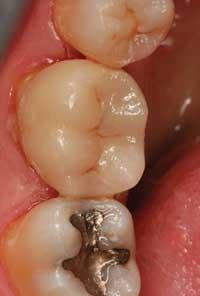

From a simple inlay to a complex, multi-unit anterior or posterior case, the CAD-CAM system is an added convenience to both clinician and patient, while adding to the patient’s comfort and reducing the financial burden absorbed by the dental practice (Figure 3).